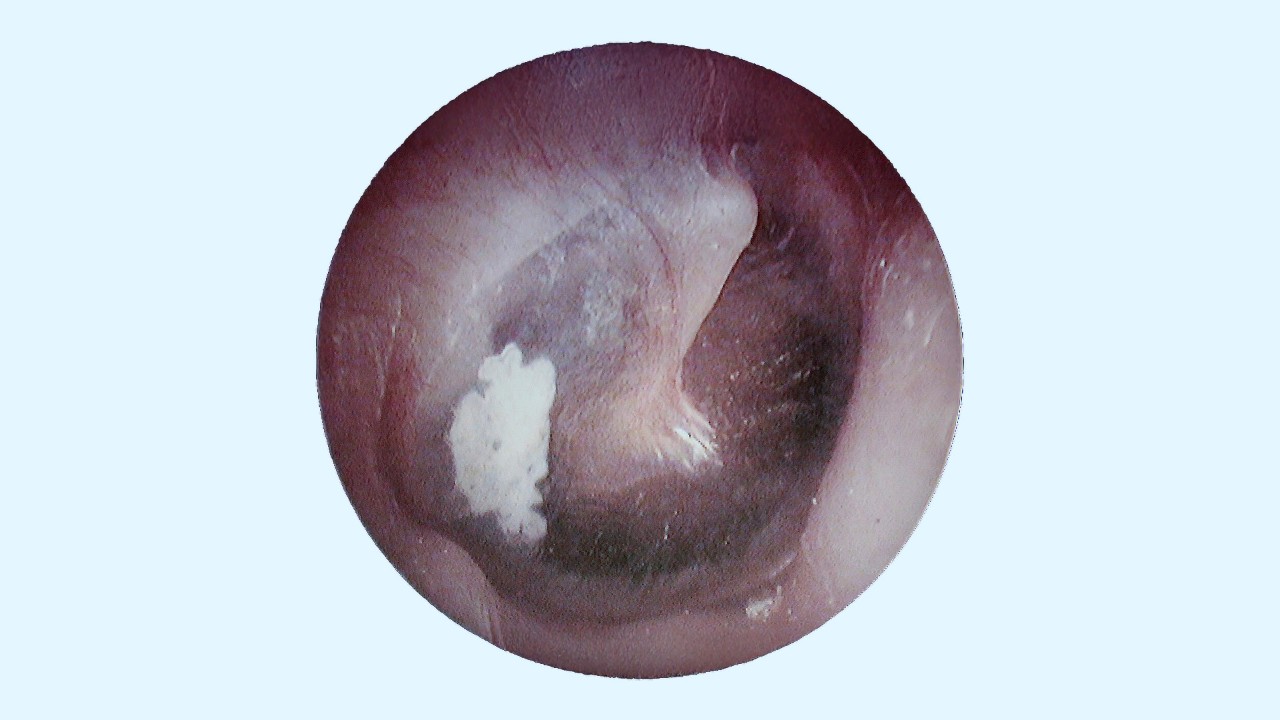

A simple tympanosclerosis definition is scarring on the eardrum, also known as the tympanic membrane. Located at the beginning of the middle ear, this thin, cone-shaped layer of tissue performs two important roles for the ears: protecting the sensitive structures of the middle and inner ear from dirt and debris and assisting in processing sound waves to hear. When the tympanic membrane becomes scarred—whether from injury or surgery—calcium deposits can build up, causing the eardrum to harden and become less flexible. This scarring appears as bright, chalk-white marks on the eardrum. Tympanosclerosis bilateral is when both eardrums are affected by scarring.

Chalky white buildup on the eardrum is another classic symptom of tympanosclerosis, but it is only detectable by healthcare professionals who can look inside your ears with special tools. If you experience ear pain or some degree of hearing loss, schedule an appointment with a hearing care professional (HCP) to examine your ears directly and determine if tympanosclerosis may be affecting your hearing.

• Ear exam: Using an otoscope—a tool that uses light and magnification to view inside the ear—your doctor will look at the eardrum for any signs of scarring.